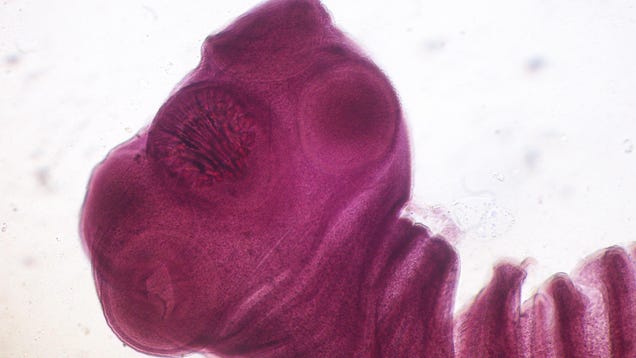

Coming down with seizures would be a scary experience no matter what, but for one unfortunate man, that experience was compounded by the discovery that dead tapeworm cysts lodged in his brain for decades were the root cause. Thankfully, his seizures were treated successfully, and the man seems to have made a recovery…